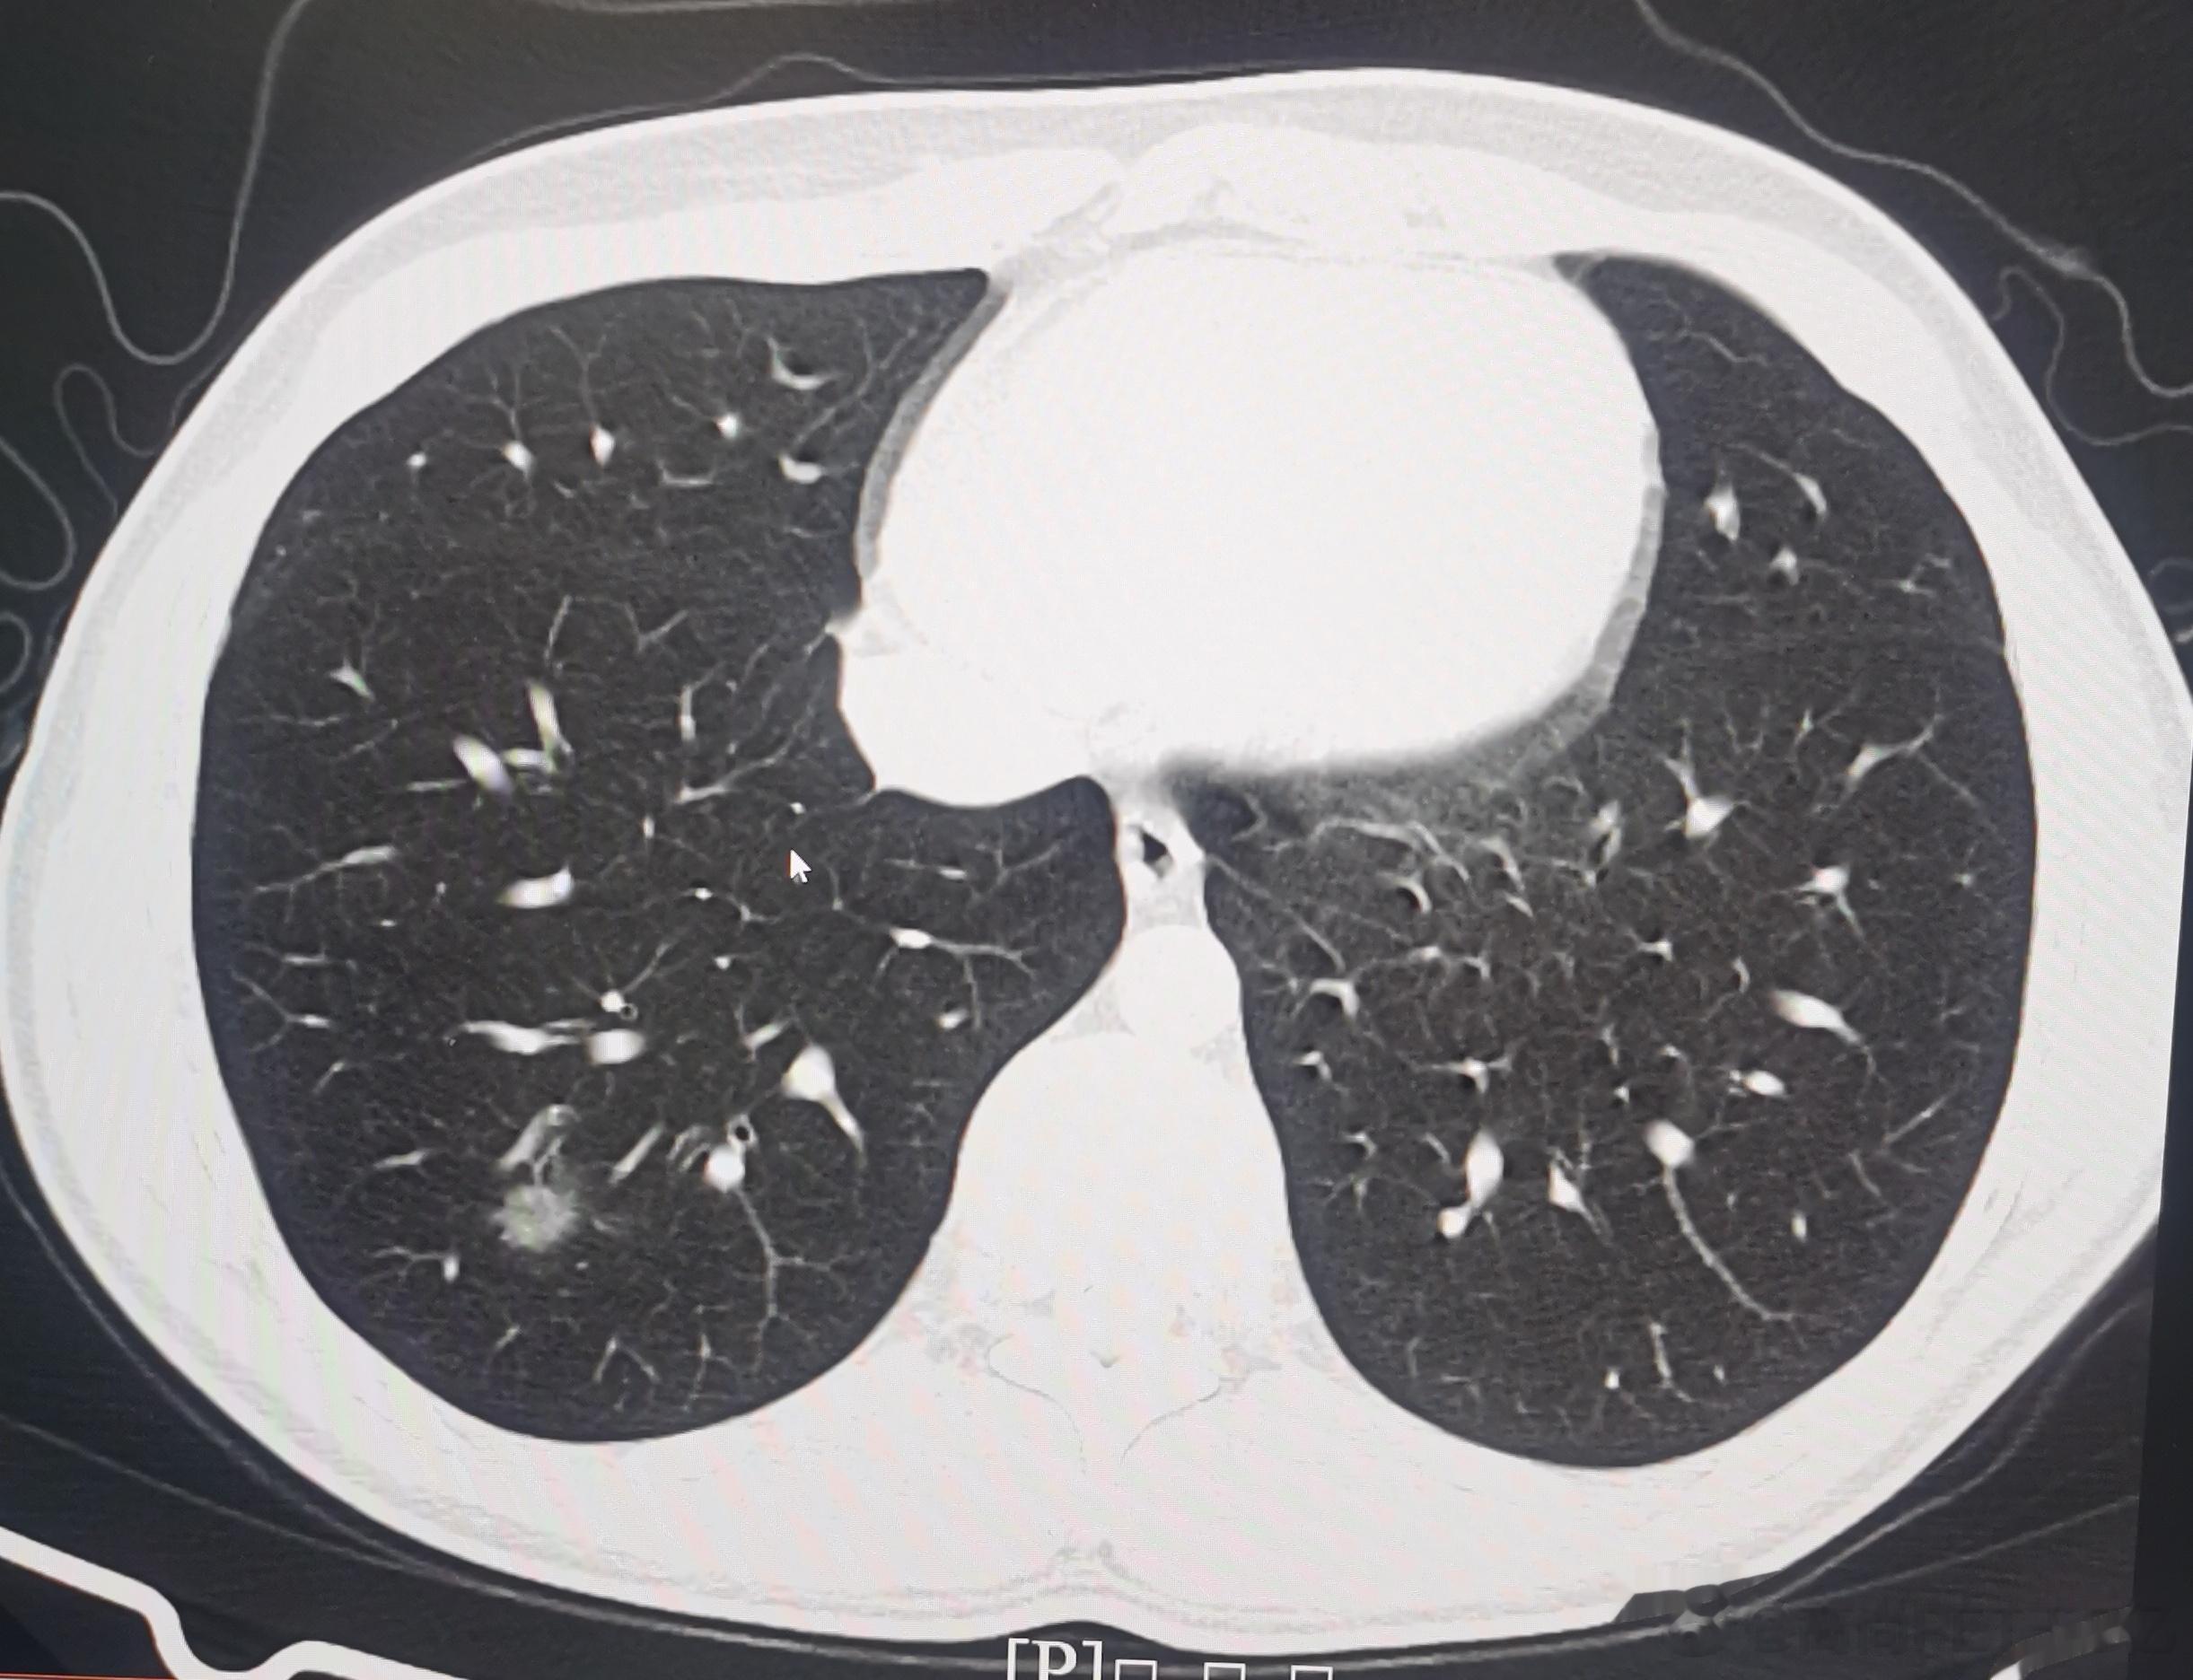

今日我们高尚影像中心新冠肺炎筛查病人是108例,其中28例有轻度新冠肺炎影像表现,检出率接近26%,最最小14岁(下面第一排CT图像),最大年龄是87岁(下面第二排CT图像),大部分人的年龄超过60例。由此可以看出,新冠病毒肺炎可能会累及各个年龄段,但主要还是60岁以上老年人群。如果新冠感染超过2周咳嗽症状还不减轻者,最好做一个胸部CT判断有无新冠病毒肺炎,这对于决策治疗方案及预测治疗效果都很关键。#老年人感染新冠后小心肺炎##感染新冠都要做CT吗#

今日我们高尚影像中心新冠肺炎筛查病人是108例,其中28例有轻度新冠肺炎影像表现,检出率接近26%,最最小14岁(下面第一排CT图像),最大年龄是87岁(下面第二排CT图像),大部分人的年龄超过60例。由此可以看出,新冠病毒肺炎可能会累及各个年龄段,但主要还是60岁以上老年人群。如果新冠感染超过2周咳嗽症状还不减轻者,最好做一个胸部CT判断有无新冠病毒肺炎,这对于决策治疗方案及预测治疗效果都很关键。#老年人感染新冠后小心肺炎##感染新冠都要做CT吗#